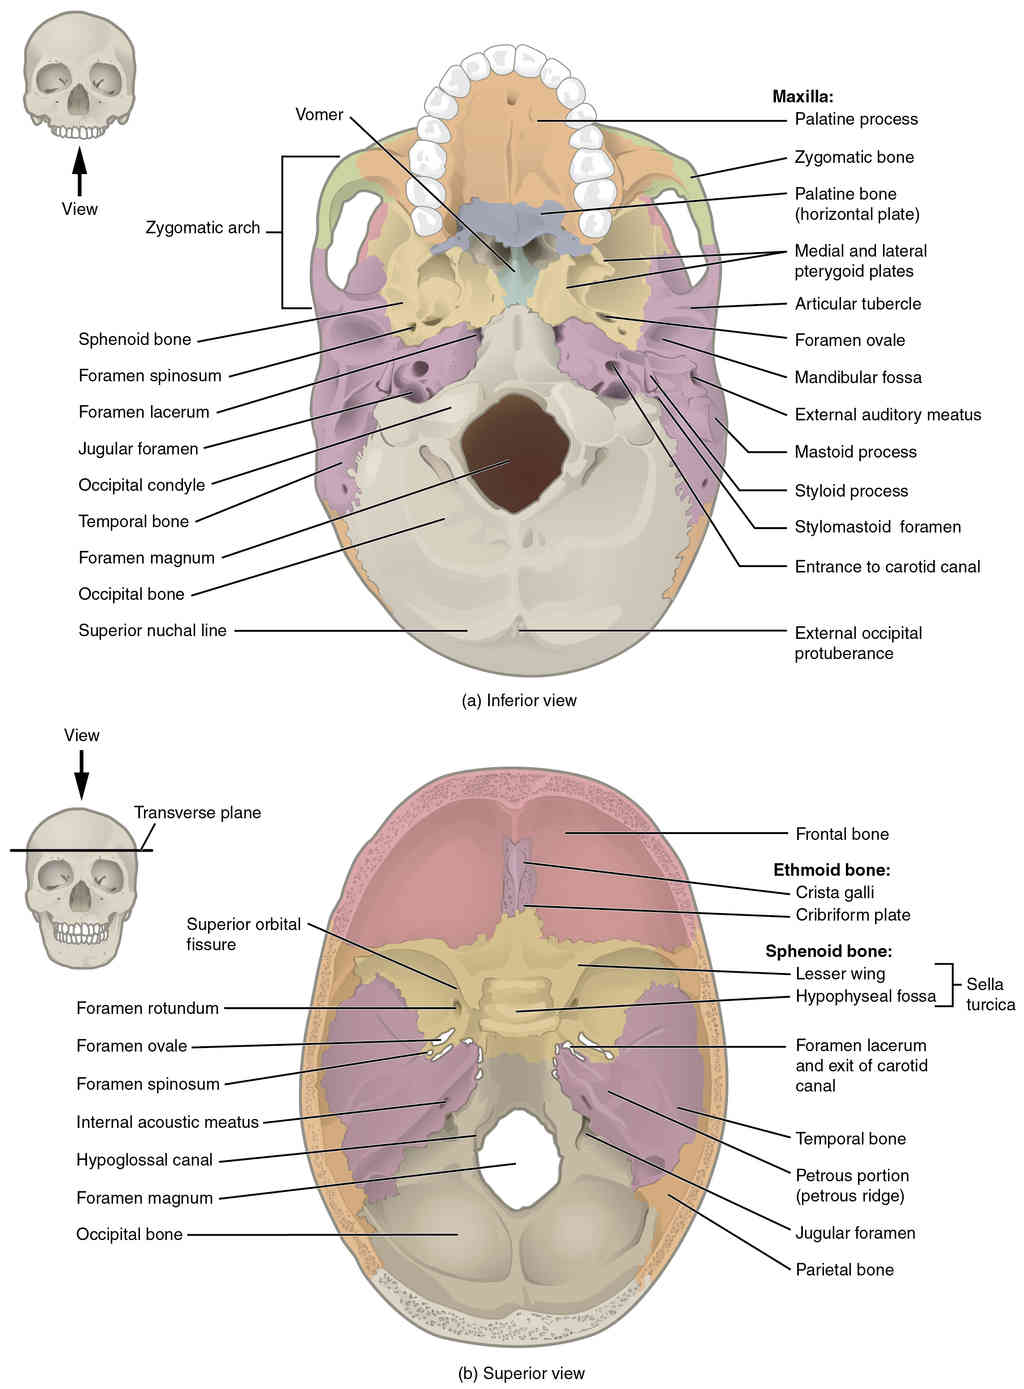

This page is under construction. For now, it is just a resource of the images found in the OpenStax Anatomy and Physiology Handbook. It wil slowly change into a revision tool. Each slide has a number. Use this to refer to the slide. When completed, it will have an unlabelled section, with labelled slides in parallel. On the unlabelled slides, write your answer and use the labelled slide to assess yourself. Keep track by also noting the number on each slide. Improvement at each attempt is important, more so than full marks on a first attempt.